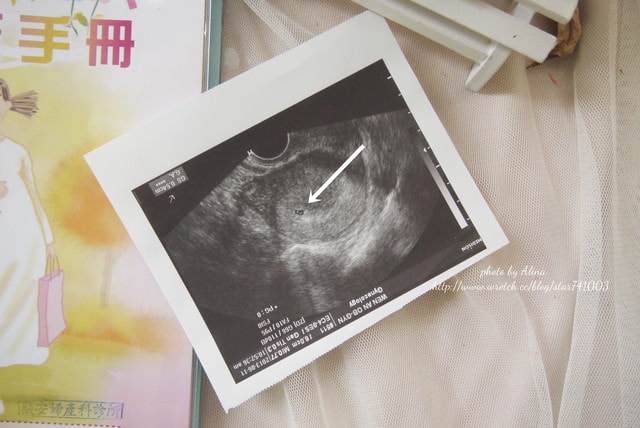

在出國的前兩天發現自己懷孕了,隔天立刻先去婦產科確定一下

不過發現懷孕時才五周所以沒有任何不適的症狀,所以出國七天完全沒影響

一切都正常喔,而且寶寶還長大了一些些♥(ˆ⌣ˆԅ)